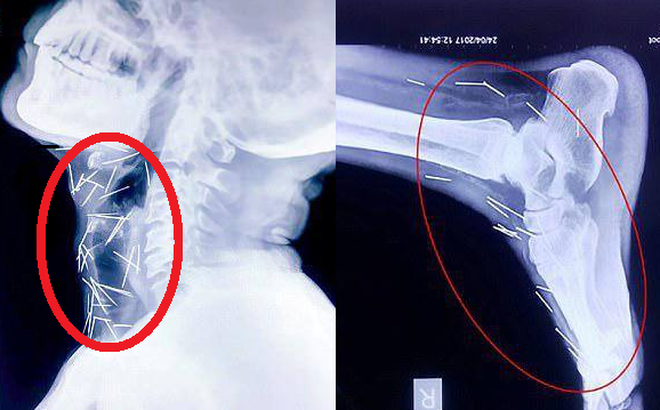

Vietbf.com - Sau khi đau chân đi khám đưa người đàn ông vào bệnh viện để phẫu thuật ngón chân cái, thì bác sĩ phát hiện trong chân ông có nhiều cây kim, khi tiếp tục kiểm tra, các bác sĩ phát hiện có tới 75 cây kim trong cơ thể, có 40 cây nằm trong cổ họng, 25 cây ở chân và 2 cây ở cánh tay, người thân của ông ta cảm thấy vô cùng sợ hãi.

Thế nhưng, trong quá trình chụp X-quang để kiểm tra tổng thể, các bác sĩ đã vô cùng sửng sốt khi phát hiện có đến 75 chiếc kim đâm trên khắp người bệnh nhân, từ cổ, vai cho đến chân.

Chân và tay bệnh nhân cũng có hàng chục cây kim khác. Ảnh: DAILY MAIL

Cho đến nay, vẫn chưa một bệnh viện nào trong số những nơi ông Meena đến thăm khám đồng ý rút kim ra khỏi cơ thể cho ông ta. Trong số 75 chiếc kim nói trên, có 40 chiếc đâm quanh khu vực họng, 25 chiếc đâm ở chân, còn lại là ở những chỗ khác.